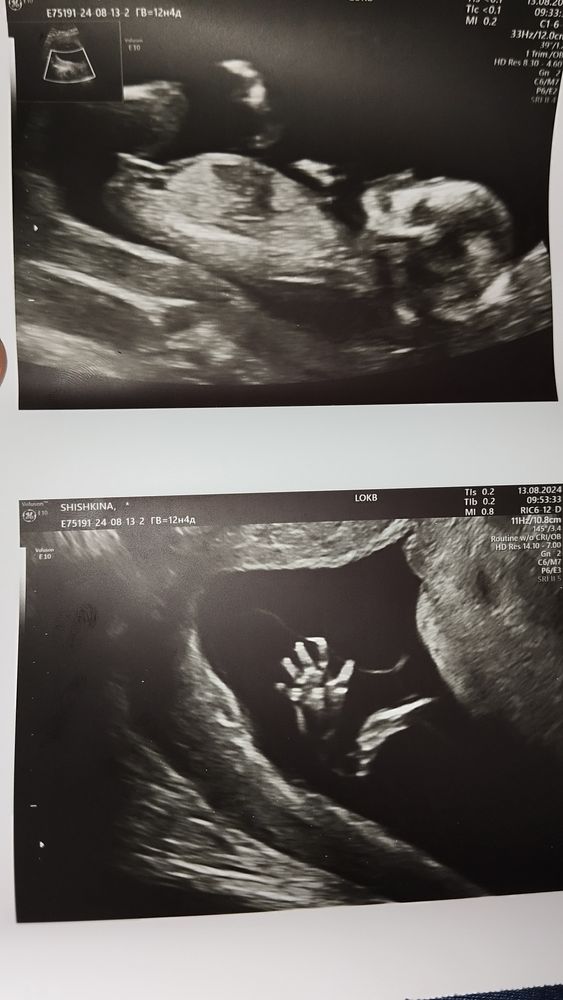

Чуть выше норм мне кажется эти показатели, но при этом риски пишут вроде низкие. Точно ли всё нормально, может кто в этом понимает? Ну и если не сложно, и есть знающие девочки, пол видно уже по узи, мальчик это или девочка? Фото прилагаю

Пр бугорку девочка

Anna Tarot-Deck, ну вот эта полоска, которую вы приняли за хоботок, это половой бугорок. Если это девочка - он параллельно расположен к позвоночнику, позже превратится в клитор, если мальчик - под углом 30 градусов примерно.

Здравствуйте! Да, завышены хгч и рарр. КТР немного больше нормы. Но тут могут быть погрешности в оборудовании и самого врача. Все остальное в норме. Риски низкие

Если волнуетесь, то всегда можно сходить на экспертное узи или сдать НИПТ. Фото лялечки просто замечательные, особенно второе! Легкой беременности вам и здорового малыша. 😊